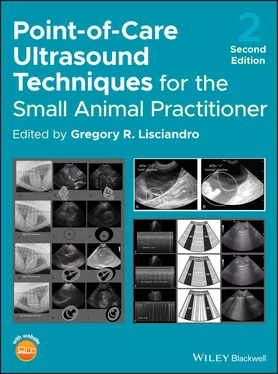

Figure 6.27. Calculi versus intestinal tract. The sonographer will readily appreciate deviations from the expected appearance of the urinary bladder at the CC view. In images (A), (C) and (E) bladder calculi are evident by clean shadowing through the far‐field and contained within the lumen of the urinary bladder. Moreover, they should settle at the “CC pouch” where free fluid would pocket being at the CC view's most gravity‐dependent region. In (B), (D) and (F) are examples of air‐filled intestinal tract that mimic urinary bladder calculi illustrating how care should be taken. By examining (and magnifying) more closely, the bladder lumen can be seen to be pushed into the lumen by the loop of intestinal tract as in (B) and (D) indicated by the cursors (V). Moreover, an abdominal radiograph may be added to the diagnostic work‐up.

Source: Reproduced with permission of Dr Gregory Lisciandro, Hill Country Veterinary Specialists and FASTVet.com, Spicewood, TX.